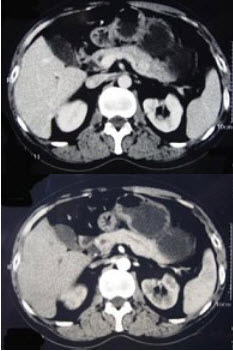

患者,女,35岁。因肥胖、乏力、高血压、多毛3年就诊。体检示向心性肥胖、满月脸、多血质面容,血压165/95mmHg。

第1题,共3个问题

(单选题)初步考虑诊断皮质醇增多症,下列哪项检查对评价肾上腺皮质功能最有价值()。

A:血浆皮质醇测定

B:血浆ACTH测定

C:24小时尿17-羟、17-酮测定

D:24小时尿游离皮质醇测定

E:血浆醛固酮测定

第2题,共3个问题

(单选题)患者午夜服用地塞米松1mg,服药后次日24小时尿游离皮质醇下降了27%,此时诊断考虑为()。

A:皮质醇增多症

B:单纯性肥胖

C:醛固酮增多症

D:垂体ACTH腺瘤

E:肾上腺皮质腺瘤

第3题,共3个问题

(单选题)进一步检查发现患者24小时尿游离皮质醇明显增高,血浆皮质醇节律异常,为明确诊断还应做下列哪一项检查()。

A:ACTH兴奋试验

B:CRF兴奋试验

C:甲吡酮试验

D:小剂量地塞米松抑制试验

E:大剂量地塞米松抑制试验